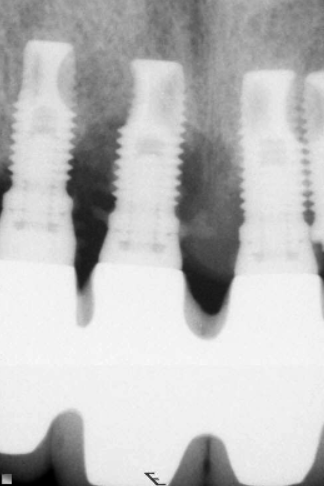

Patient Factors that May Contraindicate Fixed Implant-supported Prosthetics

(42.) Fixed-removable prosthesis.

Figure 42

(43.) Fixed-removable prosthesis.

Figure 43